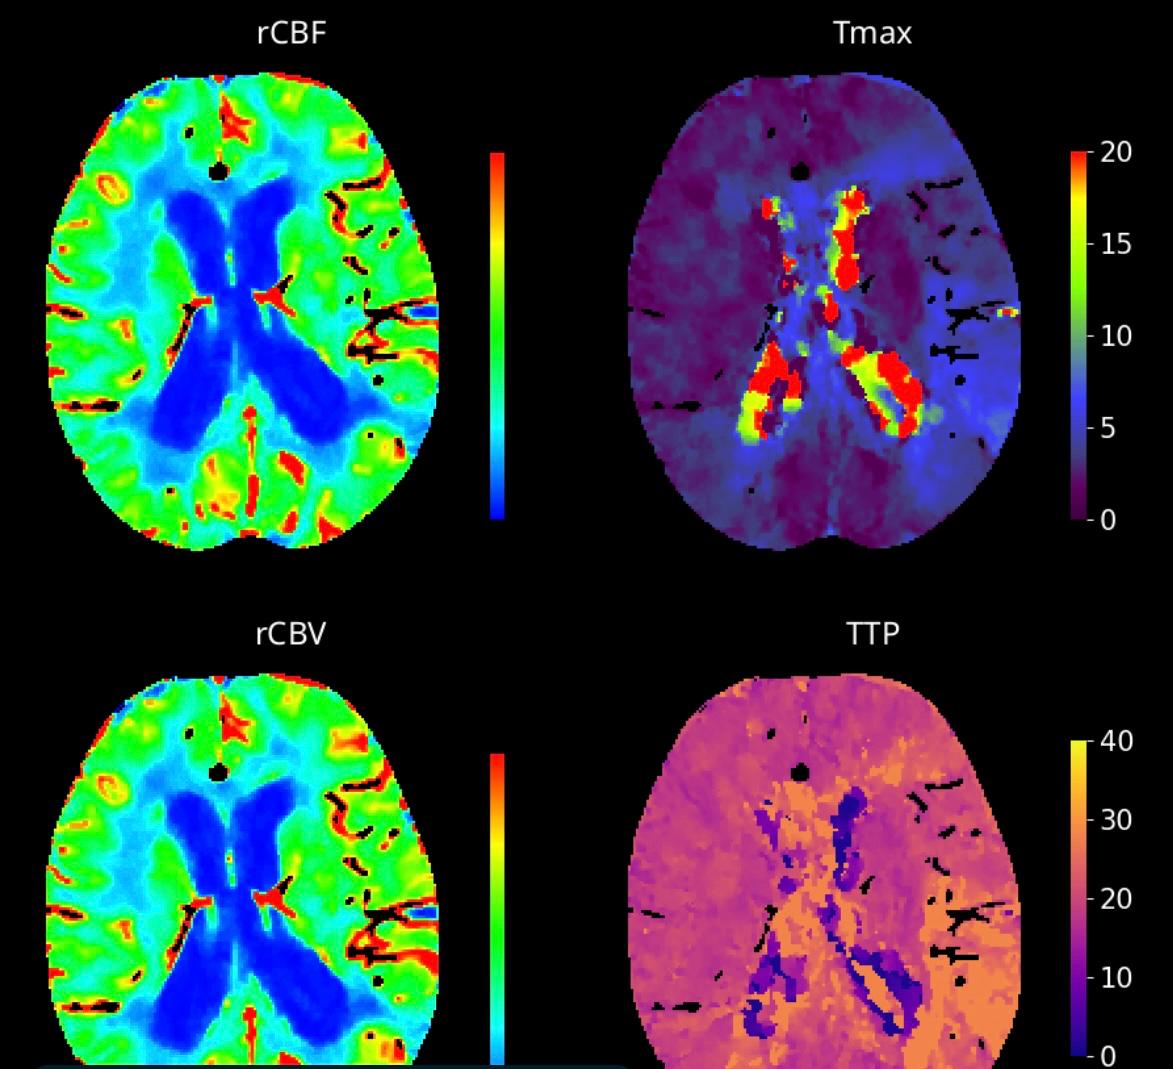

L’ultimo documento risaliva al 2017. Il nuovo protocollo prodotto dalla Asl Toscana centro aggiorna il Percorso Diagnostico Terapeutico Assistenziale (PDTA) per l’ictus ischemico, rappresentando per tutti e otto gli ospedali Stroke della Asl Toscana centro che fanno parte della Rete Ictus regionale, il riferimento scientifico ed organizzativo, nonché l’esito finale di un percorso significativo che, negli anni, ha portato ad un innalzamento della qualità. Stiamo parlando di una patologia tempo-dipendente, che in Italia costituisce la prima causa di invalidità, con circa 90 mila ricoveri l’anno e che è terza causa di morte e prima causa di invalidità nel mondo.